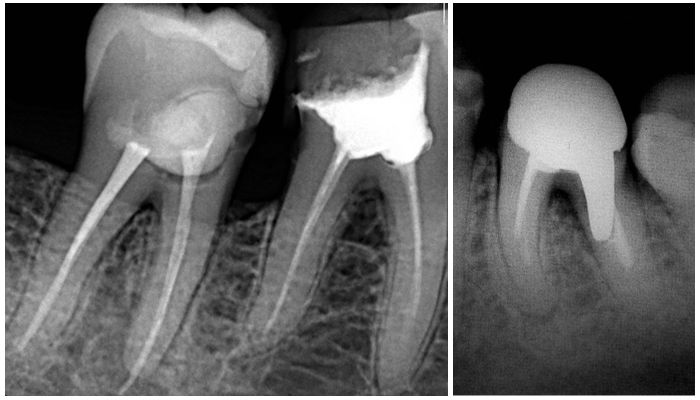

Прицельный снимок (при необходимости)

На современном оборудовании можно получить два варианта таких снимков:

- интерпроксимальный, чтобы получить информацию о том, в каком состоянии находится зубная коронка;

- периапикальный, для изучения тканей, окружающих зубной корень.

- Использование прицельного рентгена в составе обследования необходимо для уточнения информации об отдельных элементах и тканях ротовой полости, если изображение панорамного снимка трактуется неоднозначно.